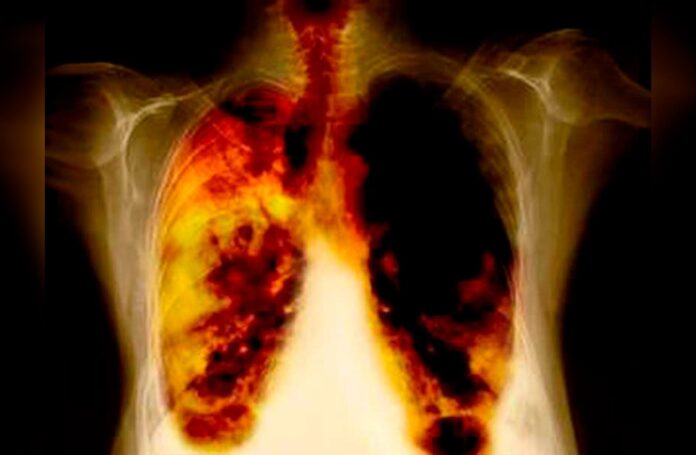

Investigadores de la Universidad de Navarra dieron a conocer que han logrado que los tumores de pulmón resistentes a la inmunoterapia respondan a tratamiento.

El cáncer de pulmón es la principal causa de muerte relacionada con el cáncer en el mundo. Según el último informe de la Sociedad Española de Oncología Médica, este tipo de cáncer es responsable del 18% de los fallecimientos por cáncer a nivel mundial, dijo la universidad.

La universidad española menciona que en el mismo informe se pronostica que en 2022, en España, serán 30.948 nuevos casos detectados por esta enfermedad.